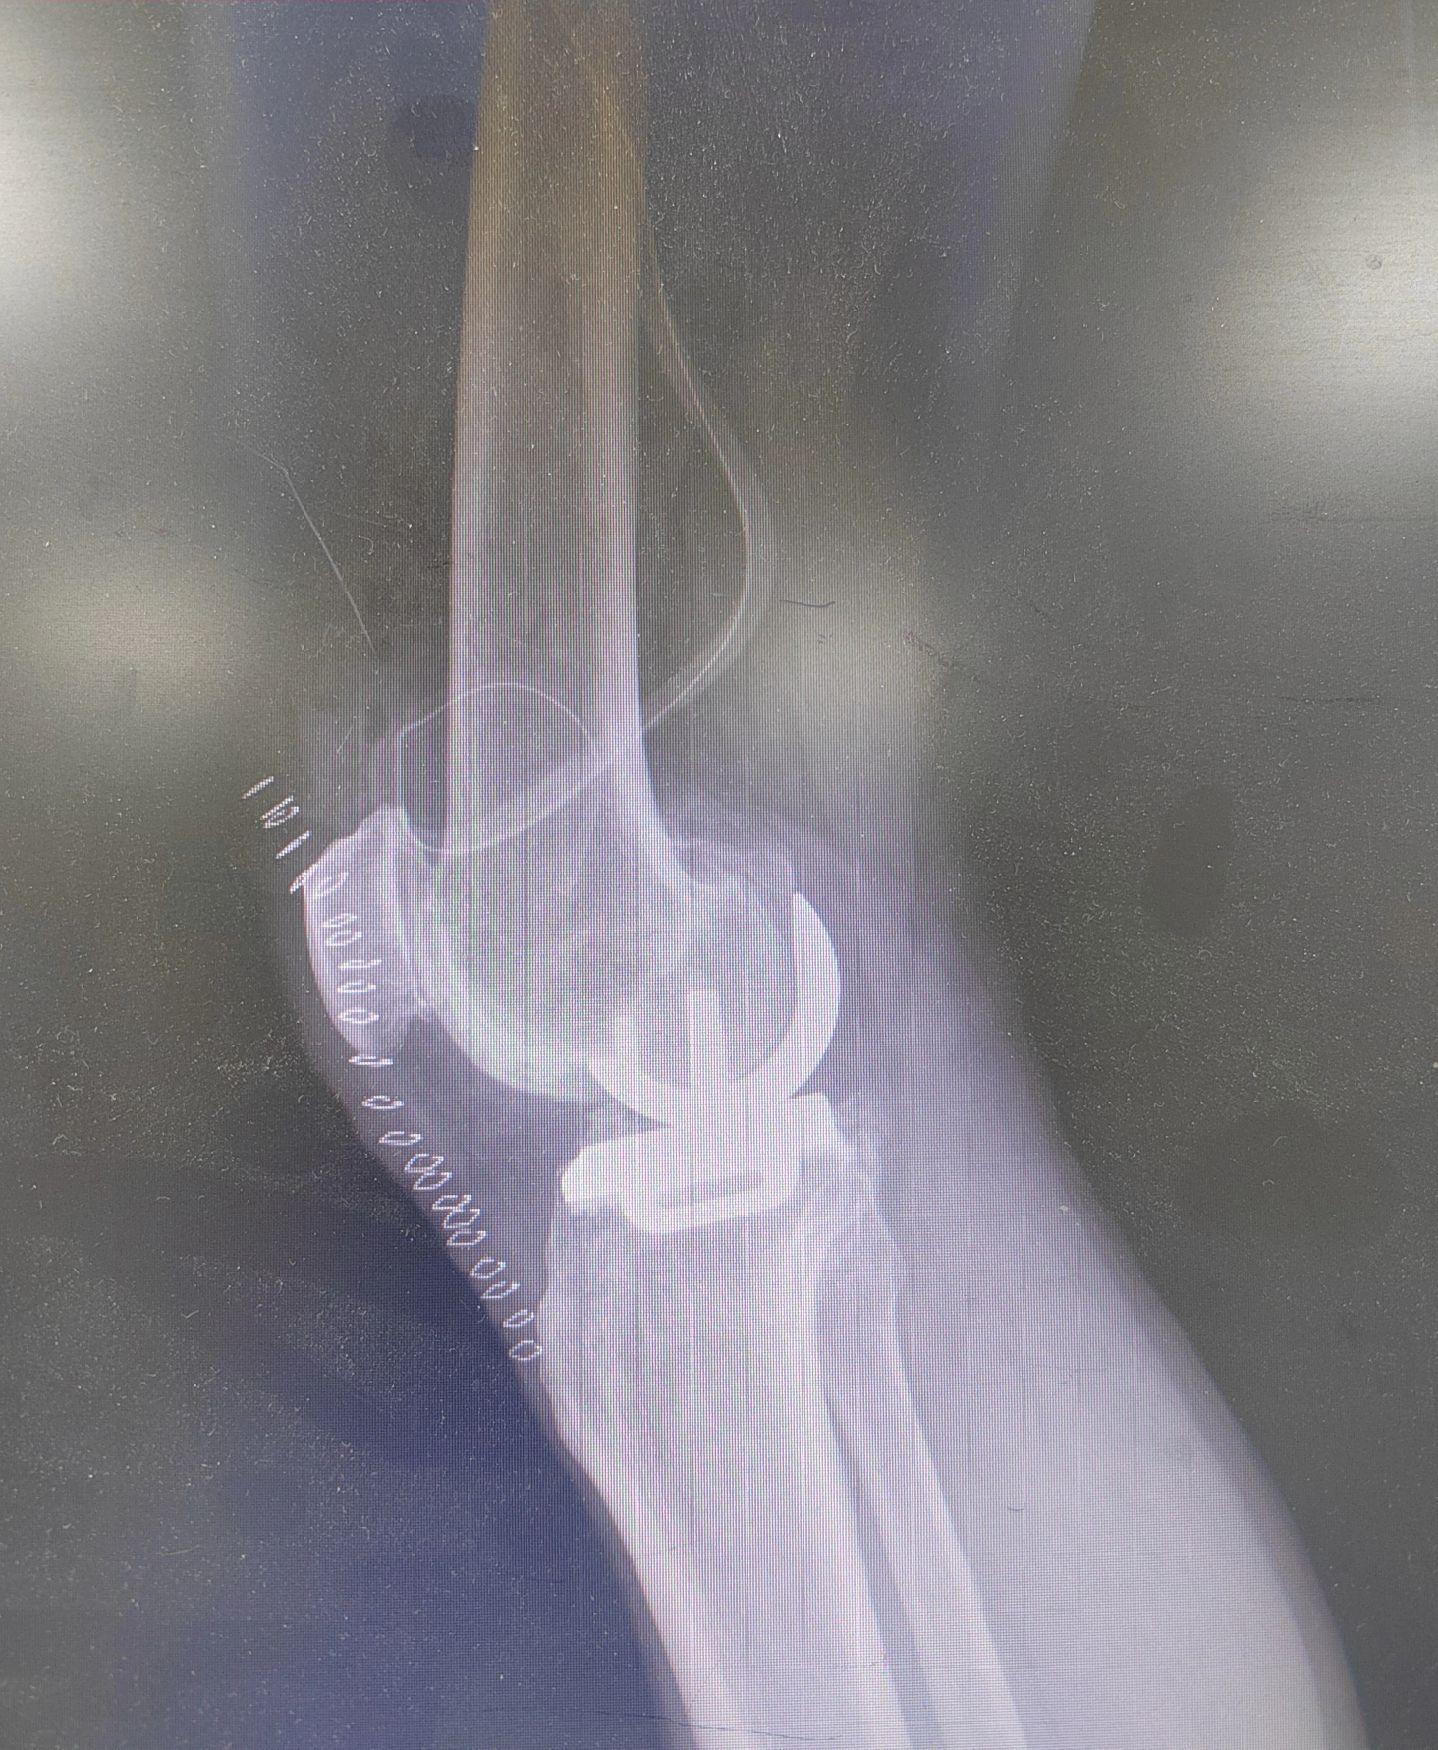

单髁置换术。(看图猜假体)每款假体都有自己的优点,不要单纯追求国产或进口,也不要单纯追求活动平台或固定平台,适合自己才是最好的。愿每一位病人都能快速顺利康复🌹